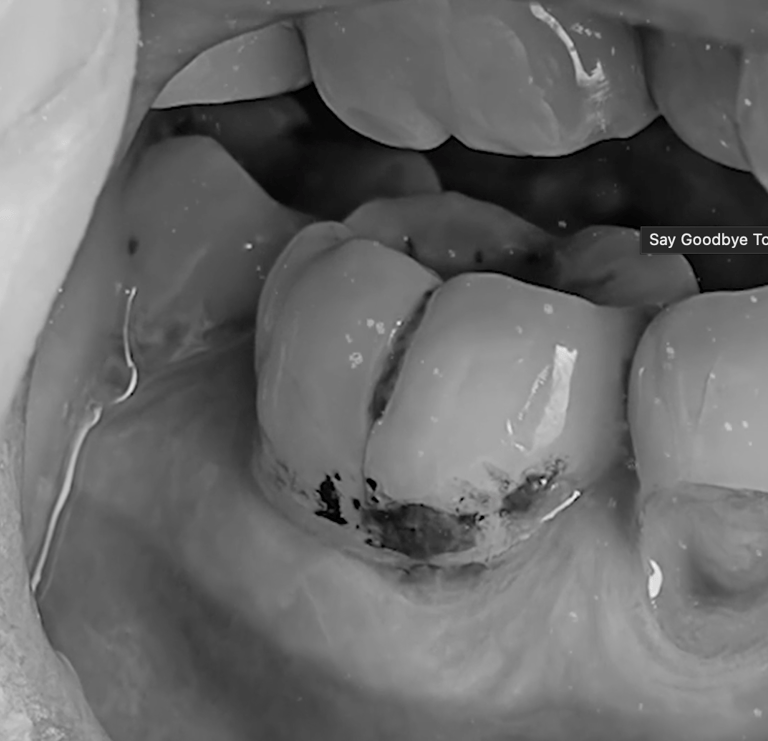

Helps prevent and repair early-stage cavities

Goodbye Cavities, Sensitivity, and Tooth Pain — Hello Healthy Smile

Larineco™ does far more than just freshen your breath — it actively protects and strengthens your teeth from within. This advanced chewing gum helps defend against cavities, plaque, and gum problems by neutralizing harmful bacteria and replenishing the essential minerals your teeth need to stay strong.